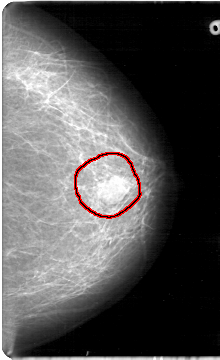

D_4083_1.RIGHT_MLO

FILE: D_4083_1.LEFT_MLO.OVERLAY

TOTAL_ABNORMALITIES 1

ABNORMALITY 1

LESION_TYPE MASS SHAPE OVAL MARGINS OBSCURED

ASSESSMENT 0

SUBTLETY 5

PATHOLOGY BENIGN

TOTAL_OUTLINES 1

BOUNDARY